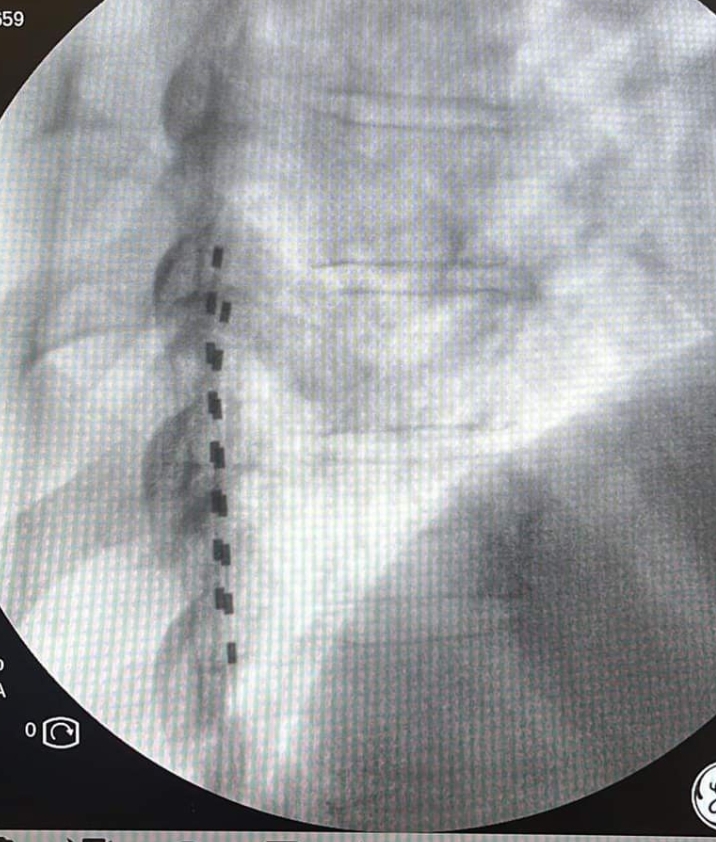

Με τον ασθενή σε πρηνή θέση, υπό τοπική αναισθησία και ακτινοσκοπική καθοδήγηση εμφυτεύονται τα ηλεκτρόδια στον επισκληρίδιο χώρο της σπονδυλικής στήλης και συνδέονται με έναν εξωτερικό διεγέρτη που δίνει τα ερεθίσματα με ένταση που επιλέγεται ανάλογα με τις ανάγκες του ασθενούς. Ο ασθενής για μια περίοδο 7-10 ημερών μπορεί να δοκιμάσει το αποτέλεσμα της διέγερσης και να κρίνει εάν αυτή καλύπτει τις ανάγκες του. Εάν η θεραπεία δεν είναι αποτελεσματική, τα ηλεκτρόδια αφαιρούνται με πολύ εύκολο τρόπο. Επί θετικής απόκρισης, έπεται η διαδικασία τελικής εμφύτευσης του συστήματος.